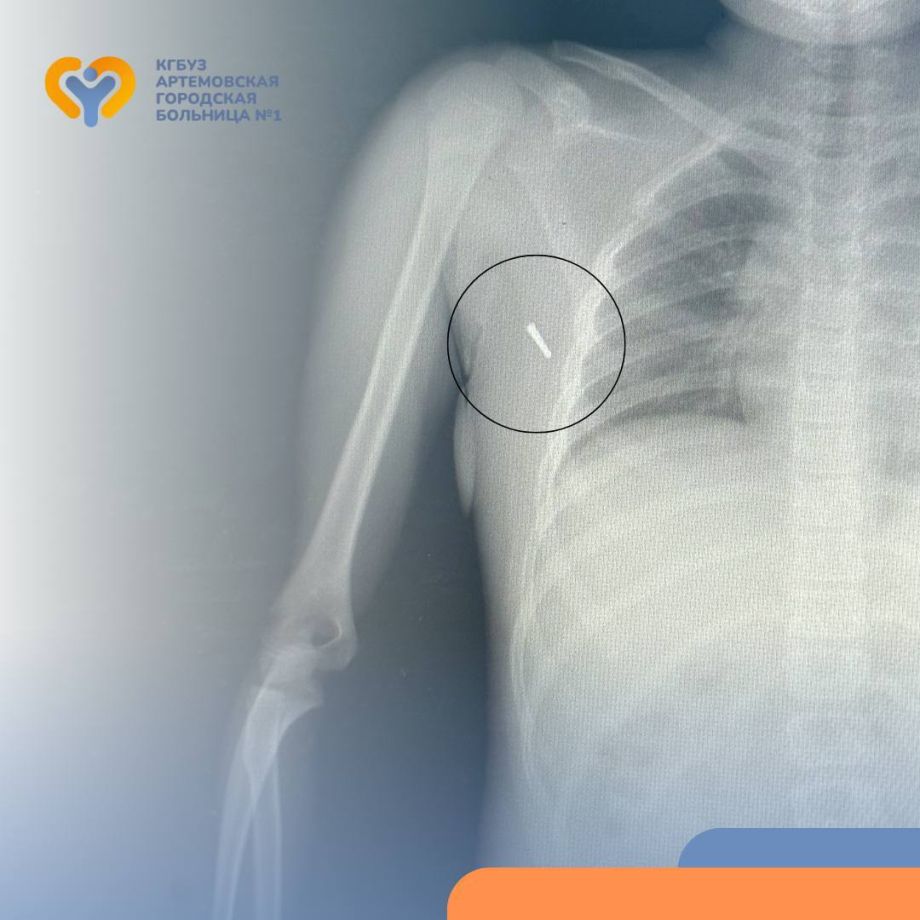

Приморские врачи спасли девочку, в которую воткнулся ртутный градусник

Врачи извлекли токсичный фрагмент, застрявший в подмышечной впадине

Восьмилетняя пациентка, получившая токсичную травму в ДТП, поступила в больницу города Артёма. Во время поездки в машине девочка держала под мышкой ртутный термометр – измеряла температуру. В результате аварии наконечник градусника отломился и застрял в подмышечной впадине ребёнка, сообщает PRIMPRESS.

Юной пациентке потребовалась незамедлительная помощь, и местные медики оперативно связались с токсикологами Владивостокской клинической больницы №2 для получения консультации. Эксперты пояснили, что главная опасность в подобных ситуациях связана с парами ртути, которые могут выделяться при повреждении градусника. При этом специалисты подчеркнули, что само по себе небольшое количество ртути, попавшее в организм, не несёт серьёзной угрозы. Это позволило врачам безопасно провести операцию по удалению наконечника.

Операция прошла успешно: травматологи аккуратно извлекли застрявший фрагмент, после чего провели необходимые контрольные анализы и сделали рентген. Для тщательного наблюдения за состоянием девочки её оставили в стационаре на несколько дней под присмотром медицинского персонала.